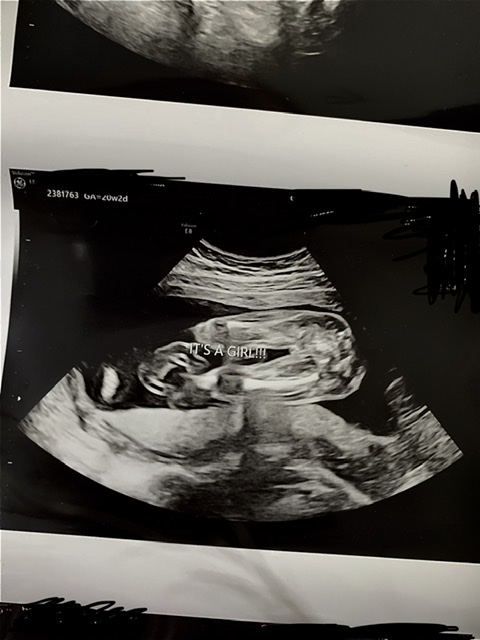

Do you see girl parts? 20w

So we went for our 20 week ultrasound two weeks ago and were told girl. They sent us home with some pictures and, while I definitely don’t see boy parts, I also don’t really see the typical girl parts. Is this just a bad picture for this? Obviously I’m not an expert but I feel like on the screen during the ultrasound I didn’t see anything more conclusive. I’m going for a follow up because of my placenta’s location in a few days and I want to be mentally prepared if the tech may not have been 100% sure. Thanks in advance!Name:  911C0B29-ED5D-411E-B2C8-5BA1D16D540A.jpeg

looks like a girl to me the legs are close together so everything is squashed but you can still see the line down the middle, hope everything goes ok with your follow up scan.

I would be shocked if that wasn't a girl!!! Huge congrats!

Thank you both for looking! Follow up this morning confirmed my healthy baby girl!